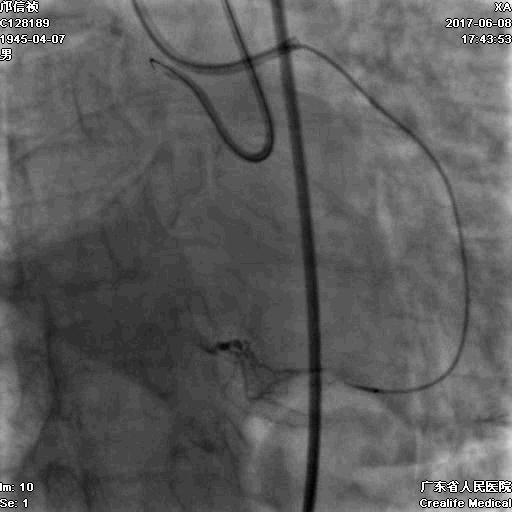

RRA:6F AL0.75 GC –RCA;

RFA:7F XB 3.5 GC—LCA 150cmcorsair

正向130cmFinecross微导管支持下尝试送PILOT150、Gaia 2导丝无法通过RCA闭塞段

SION导丝通过侧枝

逆向导丝:更换Gaia2

正向导丝:Gaia2,PILT150

正向导丝knuckle

2.5*15mm球囊扩张,逆向导丝尝试,但未能进入正向GC

1.正向2.5*15mm球囊扩张,Reverse CART

2.Guidezilla延长导管辅助下,逆向导丝进入正向GC

1.更换RG3导丝

2.GC送入普通导丝,保护LM